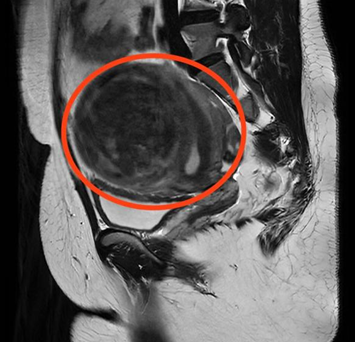

妇科门诊就诊。经过B超检查显示,曹女士子宫左侧壁肌瘤内可见102*88*92mm的包块,考虑为子宫肌瘤。面对如此“巨大”的肌瘤,曹女士忧心忡忡,以为只有通过开腹手术才能将其切除,手术过程及术后遗留的疤痕让她既害怕又焦虑。

CT检查显示子宫左侧壁巨大肌瘤